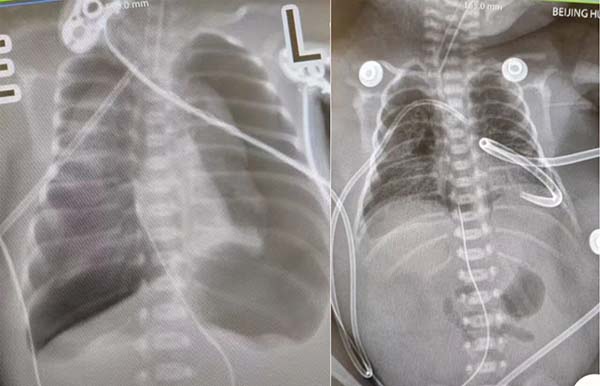

小星星稚嫩的肺,像未充气的气球,不堪重负。好不容易把生命体征维持在正常范围,重症肺炎的并发症发生了。先是右侧大量气胸,让每一次微弱的呼吸都变得艰难,心脏明显受压,心率、氧饱和度均明显下降,生命悬于一线!韩露艳副主任医师负责指导抢救,立即请胸外科急会诊,胸外科主治医师胡鹏程和吴炳群进行右侧胸腔穿刺后,右侧气胸明显缓解。然而一波未平,一波又起,患儿左侧也发生大量气胸,随后立即进行负压引流,水封瓶里就像“煮沸的开水”一样,持续大量气体引出,两根细小的引流管,为患儿不堪重负的肺赢得了扩张空间。

胸片显示大量气胸(左);引流后气胸缓解(右)